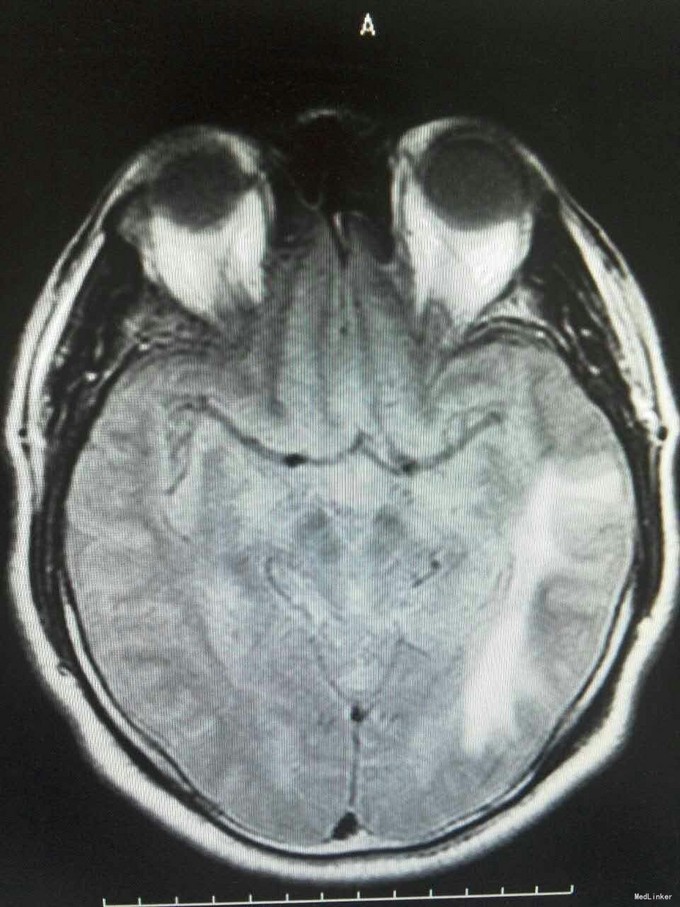

患者姜磊,男,49岁,主因"发作性视野缺损、失认8年余"于2015-11-20再次入我院,患者缘于8年前无诱因出现发作性视野缺损,伴阅读能力、理解力、认知能力下降,每次发作症状持续约3-5分钟左右,可自行缓解,无意识丧失、视物旋转、言语不利,无肢体活动障碍、大小便失禁。入院复查头颅MRI平扫+增强示:原左侧小脑幕、颞叶炎症治疗后,与2014-09-10日片比,病灶较前增多、增大。8年来间断在我院以:颅内非特异性炎症、症状性癫痫、高血压病 住院治疗,患者症状时轻时重,病灶反反复复,激素治疗有效。 病史汇报: 于2007年12月12日因"发作性视野缺损、失认1月"入我院,查头颅MRI示:左侧幕上颞底片状异常信号,并局部强化,考虑:炎症可能,肿瘤不排除;行腰穿检查,颅压120mmH2O ,外观清亮,脑脊液常规、生化均正常。脑电图轻度异常。给予复方磺胺甲恶唑片、青霉素、阿昔洛韦、激素(醋酸泼尼松片)等治疗。 2008年1月8日复查头颅MRI示:原左侧幕上颞底炎性病变范围缩小,综合考虑原颅内病变为炎性病变。于2008年1月19日出院,共住院37天。出院后仍间断出现发作性视野缺损症状。于2008-5-6复查头颅MRI示原左颞叶病变范围有缩小,支持局灶性脑炎的诊断。于2008.5.22~6.12予青霉素480万单位2/日巩固治疗30天。鉴于反复出现发作性视野缺损症状,于2008.6.5诊断性服用卡马西平片后上述症状未再发作,于是坚持服用卡马西平片(0.1g3/日)1年,服药期间未再出现发作性视野缺损症状。 于2012-05-29再次因"发作性双眼右侧视野缺失、闪烁感6天"入院,查头颅MRI示:原左侧幕上颞叶病变治疗后改变,考虑为炎性病变,结核可能。行腰穿示压力125mmH2O,脑脊液常规:颜色:无色,透明度:水样透明,潘氏试验:阴性,红细胞计数:80×106/L,白细胞计数:0x106/L,单个核细胞75%,多核细胞20%,脑脊液生化:蛋白508mg/L,葡萄糖3.3mmol/L,氯化物115.4mmol/L。脑电图印象:基本节律为低-中幅的α波, 频率调幅调节欠佳,分布可,左侧枕区波幅可见较右侧枕区减低。头前区可见少量低幅θ波及β波。深呼吸中见4-5hz慢波增多,有时呈短至中程节律,头前区为著,左侧偏胜。深呼吸后恢复好。睁闭眼试验:半抑制。闪光刺激:未见异常。脑电地形图:以α功率为主,可见θ功率。结论:轻度弥慢性异常脑电图及地形图;给予改善循环、营养神经、活血化瘀、脱水、激素等对症治疗。住院期间未再出现上述发作。 于2013-1-5再次因"发作性双眼右侧视野缺失、闪烁感1周。"入院,行头颅MRI示:左侧颞叶病变治疗后改变,与2012-07-24日片比,左侧小脑幕病变较前增大,左侧颞叶出现新病灶。给予改善循环、营养神经、活血化瘀、抗癫痫、抗感染(青霉素)、激素冲击(甲强龙)治疗后病情好转,于2013-4-15复查头颅MRI病灶再次缩小。患者出院后上述症状仍偶有发作。 于2014-5-12、2014-9-10复查头颅MRI病灶有增大趋势,再次给予抗炎(激素)等对症治疗后,于2014-11-24再次复查头颅MRI示:原左侧小脑幕、颞叶病变治疗后改变,与2014-09-10日片比较,较前明显缩小,水肿较前明显减轻。